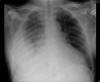

Neumonía basal.